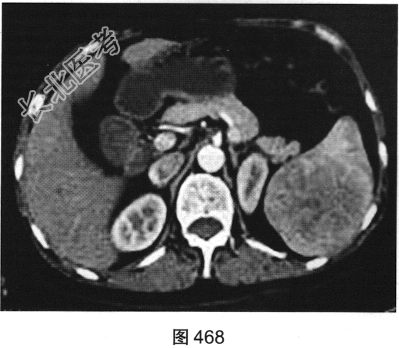

- 多项选择题2.[提示]患者行CT动态增强扫描,如图467~图469所示。对CT图像描述正确的是( )

A、病灶内见条索状钙化灶

B、病灶动脉期无强化

C、CT平扫呈不均匀稍低密度

D、左肾被病灶侵犯

E、病灶门脉期显著强化

F、病灶边界清晰,具有包膜